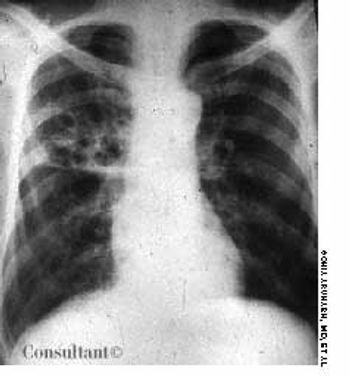

A 2-month history of cough sent a 62-year-old woman for medical evaluation. The patient denied fever, chills, and rigors but reported seeing streaks of blood in her sputum during the past month. The patient had undergone a right nephrectomy 4 years earlier for renal cell carcinoma.